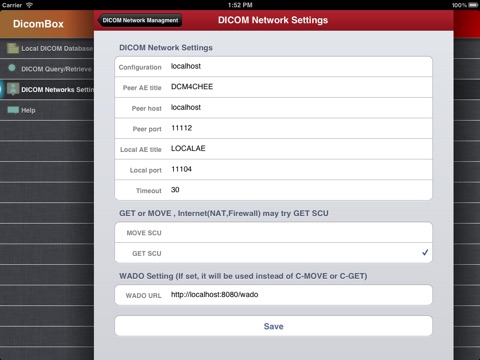

"DicomBox" is a DICOM software for iOS: DICOM is the digital standard for storing and transferring medical images. DicomBox allows downloading and manipulating series of images directly on your iOS device. DicomBox is capable of displaying images from all imaging modalities in their native standard DICOM format used by the medical/scientific industry. DicomBox is a fully DICOM-compliant listener that can receive images from any DICOM imaging device through WiFi/3G networks.